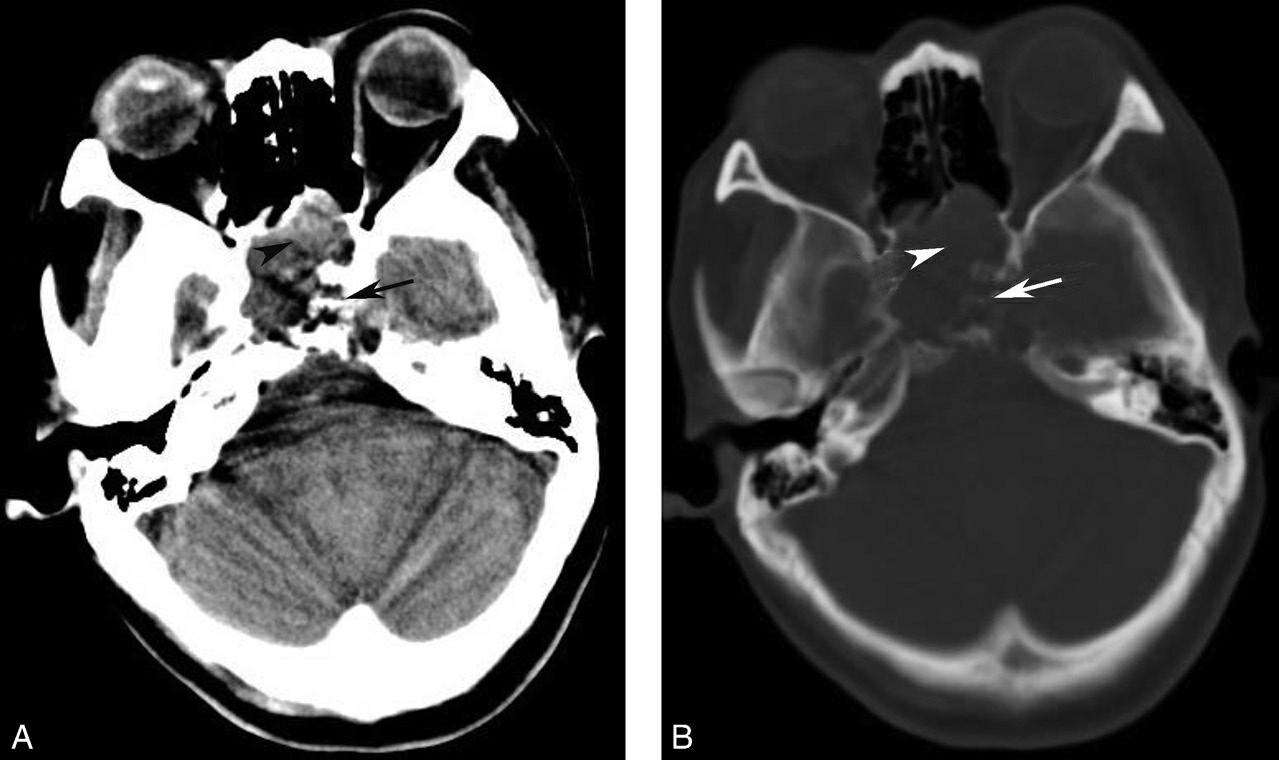

破裂孔、卵圆孔、棘孔及斜坡等均为重要的解剖结构,临床常见疾病如鼻咽癌常侵犯上述结构(图1-2-3)。颈静脉孔区较常见的肿瘤为颈静脉球瘤,常伴有颈静脉孔及其邻近骨质的破坏(图1-2-4)。

图1-2-3 鼻咽癌颅底骨质破坏

A.横断面;B.横断面(骨窗)

骨窗示左侧岩尖、斜坡、左侧蝶骨大翼骨质破坏、受侵(白箭),肿瘤经破裂孔侵入颅内(黑箭头)